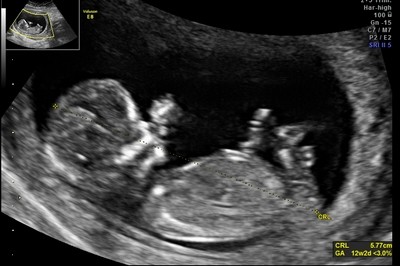

Ale najważniejsze - Dzidzia ma prawie 5 cm, wierciła sie i skakała jak oszalała, wierzgała rączkami i nóżkami